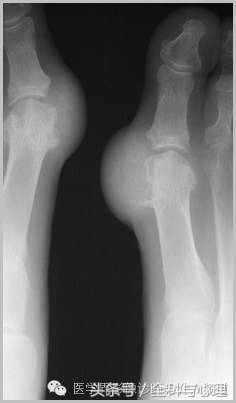

4、痛风石

为尿酸盐沉积形成,发生在关节周围软组织、包括韧带、肌腱、滑囊,眼、耳、鼻、喉、皮肤, 50%的钙化为X线平片可见。

痛风石,可见软组织肿胀及钙化灶。